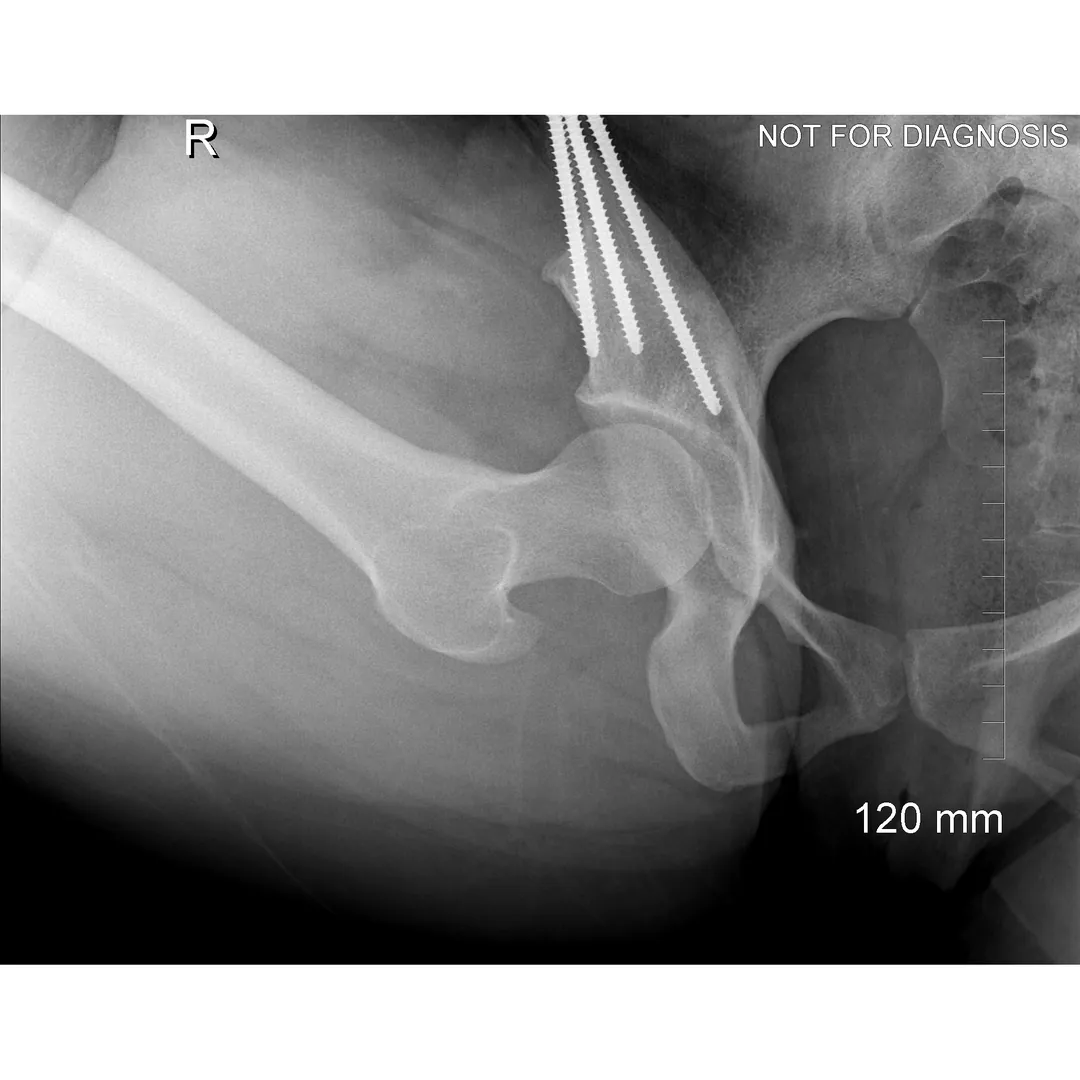

During a PAO, the surgeon carefully cuts the bone around the hip socket and repositions it to provide better coverage of the femoral head. The socket is then fixed in its new position using screws. The goal is to improve hip stability, reduce pain, and preserve the patient’s natural hip joint.

Diagram 3: Hip After Periacetabular Osteotomy (PAO)

• Acetabulum repositioned to improve femoral head coverage

• Load more evenly distributed across the joint

• Screws shown securing the acetabulum in its new position

These diagrams are commonly used in clinic to help patients visualize the problem and understand how PAO corrects hip mechanics. Dr Grammatopoulos will review your X-rays alongside these illustrations to explain your individual anatomy and surgical plan.